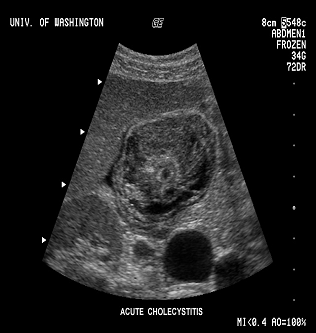

·              1 этап - Сестринское обследование <#"577077.files/image001.gif">